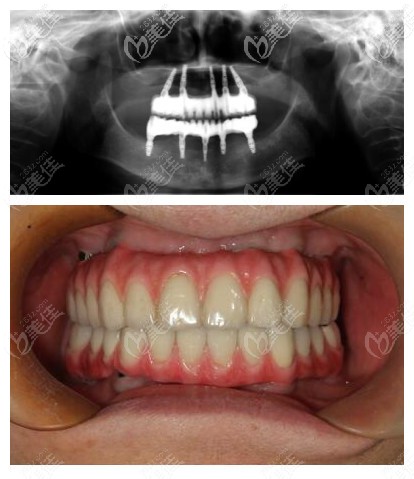

关院经典的全口即刻负重种植▼